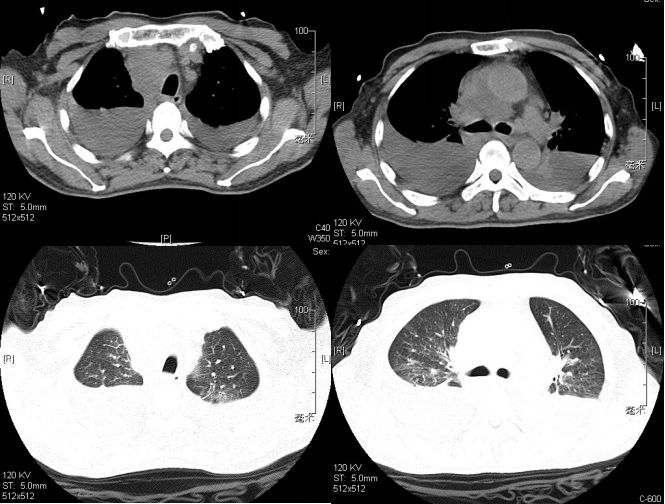

老王入院后,给予常规抗感染对症治疗,气喘进行性加重,短期内出现双侧大量胸腔积液,大量心包积液伴双下肢浮肿,继发呼吸衰竭、心功能衰竭。复查胸部CT示双侧胸腔积液和心包积液较前明显增多(图5)。

图5. 2016.1.7复查胸部CT提示胸腔积液快速进展

2016年1月28日 胸部CT示病变明显吸收(图8)。

图8. 2016.1.28胸部CT示抗真菌+激素治疗20天病灶明显吸收

遂予以出院,回当地医院继续抗真菌治疗。出院后随访至今,患者病情稳定(图9)

图9.2016.5.5当地医院复查胸部CT示双侧胸水及心包积液明显吸收,纵隔淋巴结明显缩小(抗真菌治疗4月)